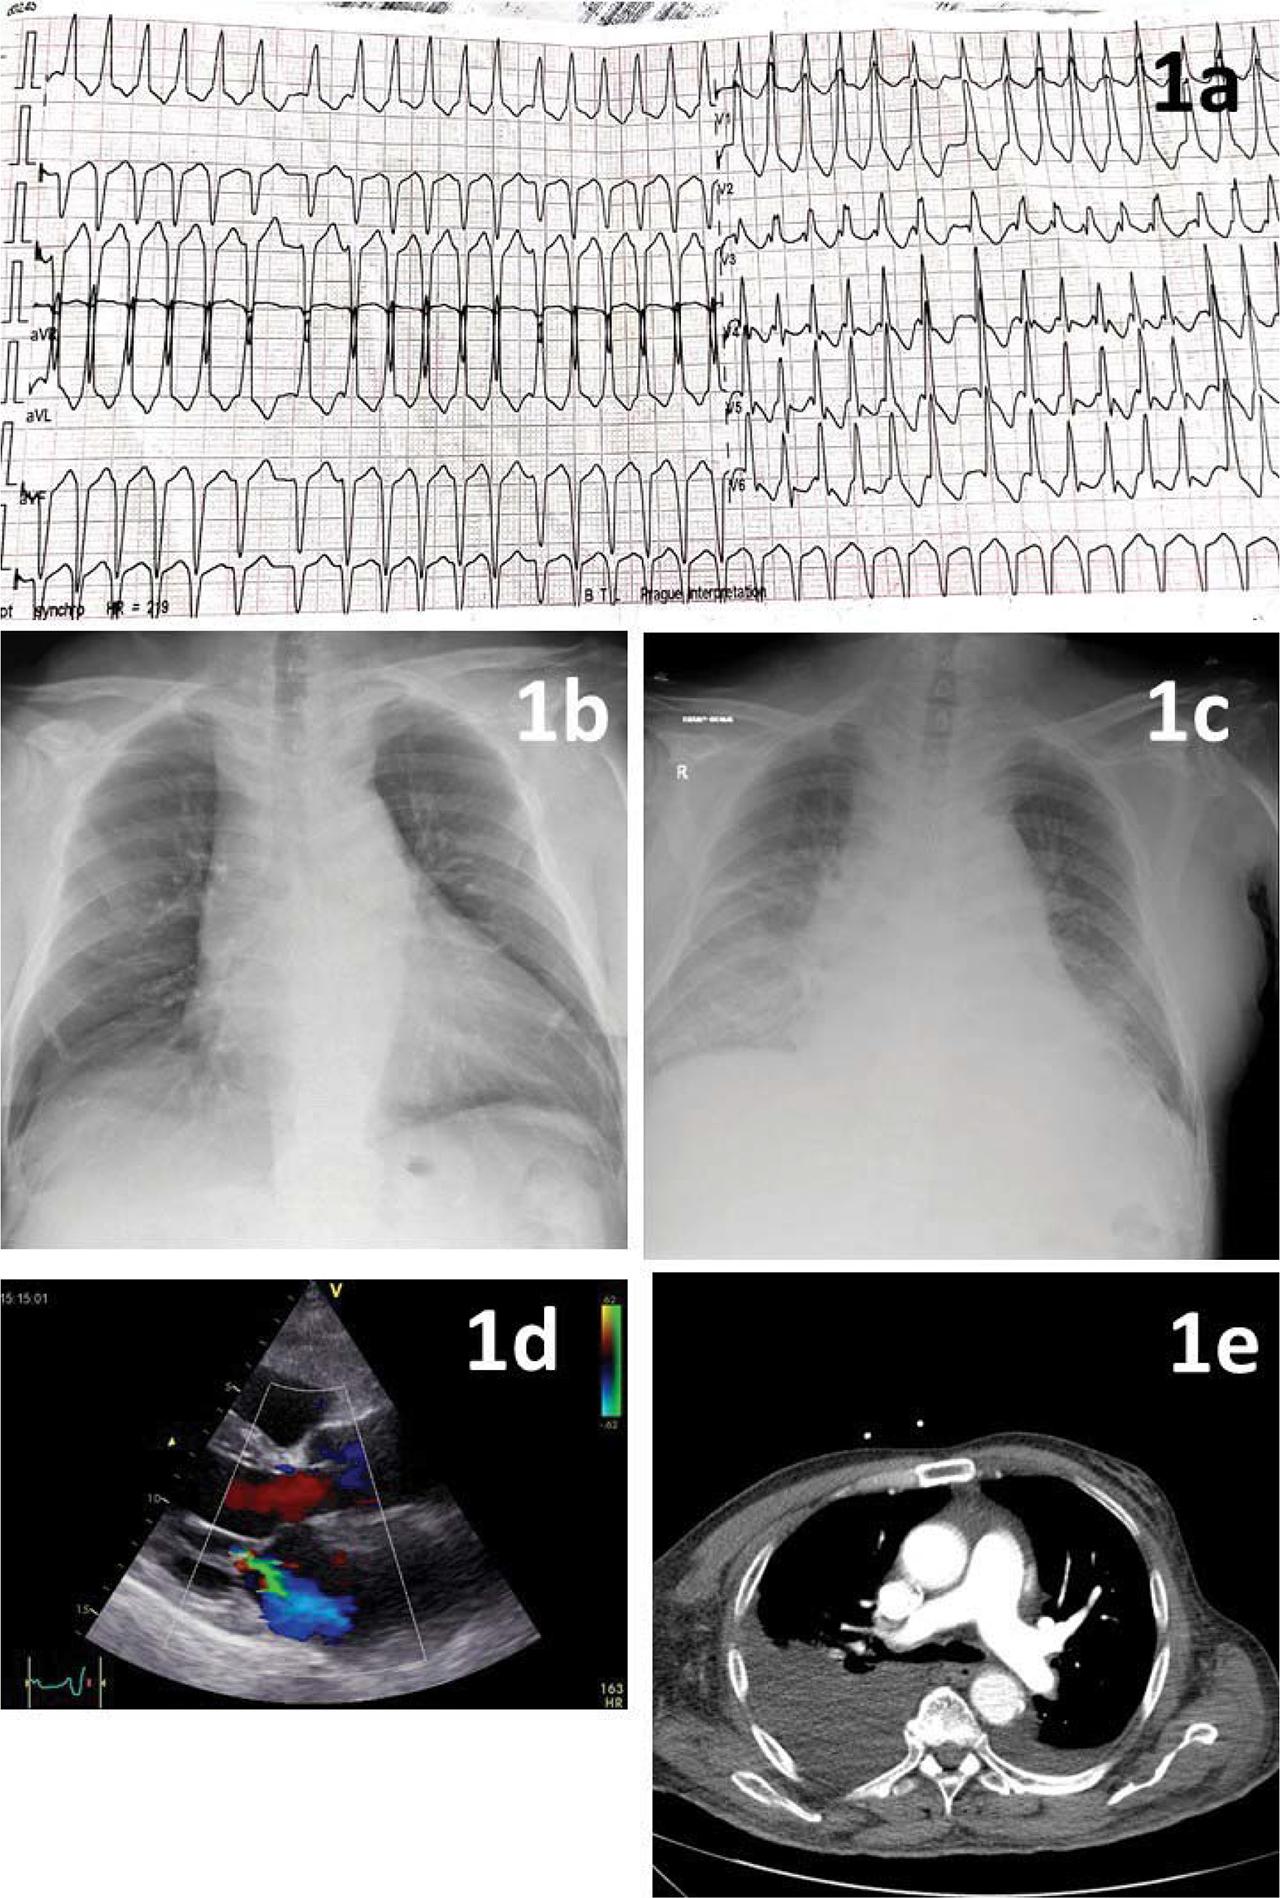

Figure 1